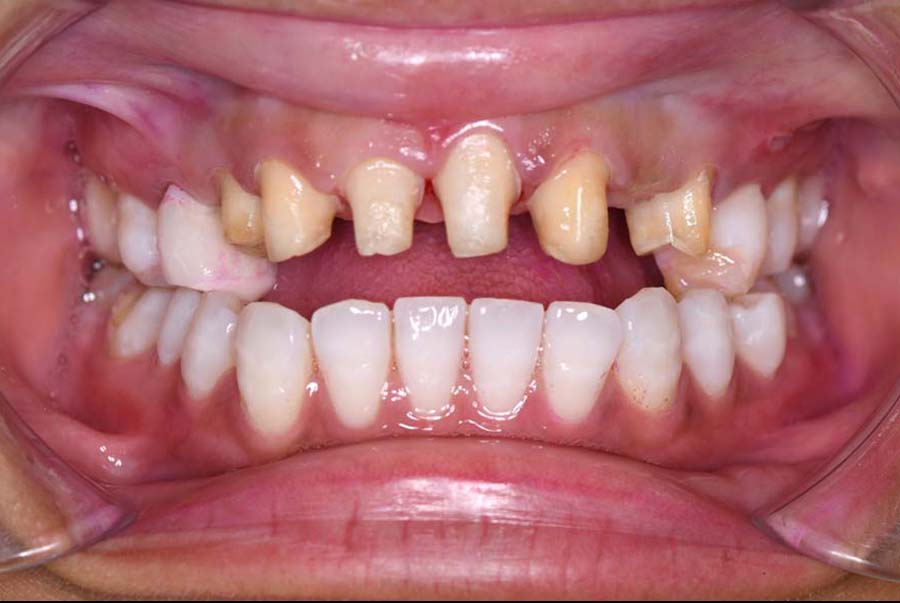

バイトアップ後

![]() |